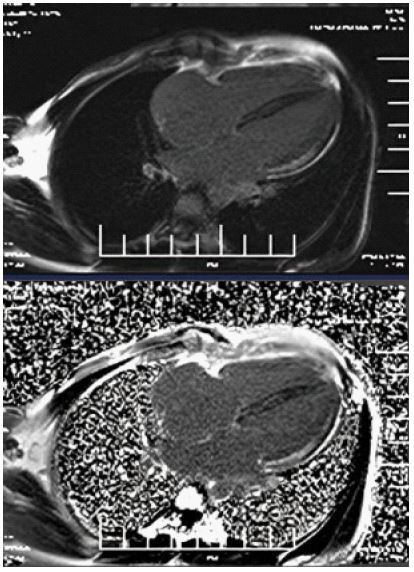

A 33-year-old female with no prior comorbidities presented with a seven-day history of high-grade fever, chills, rigors, dyspnea, and cough with borderline blood pressure requiring inotropes. Preliminary evaluation with ECG revealed sinus tachycardia and a 2D echo revealed global LV hypokinesia and severe Left ventricular dysfunction with LVEF of 30%. Initial laboratory investigations revealed elevated troponin with elevated NT-Pro-BNP suggestive of myocardial injury and acute heart failure, anemia (Hb: 9 g/dL), and elevated TSH (7.8 mIU/L), and mild renal dysfunction. The patient was admitted to the Intensive Care Unit and was treated for Heart Failure. A cardiac MRI was done, and it showed significant mid-myocardial Late Gadolinium Enhancement (LGE) in the LV free wall, sparing the endocardium and epicardium. While mid-myocardial LGE is commonly associated with myocarditis, it can also be seen in other conditions such as sarcoidosis, dilated cardiomyopathy, and Anderson Fabry disease. In this case, the findings were interpreted in conjunction with the clinical presentation, including recent febrile illness, elevated troponin, and rapid LV dysfunction. The imaging met the revised Lake Louise Criteria, supporting a diagnosis of probable myocarditis (Figures 1-3). Patient was started on IV Methylprednisolone 1 g daily for three days and then started on Oral prednisolone 1 mg/kg/day. Four days into her illness, she experienced two syncopal episodes and was found to have bradycardia with a heart rate of 30/min. An ECG revealed a complete heart block (Figure 4) with a wide-complex escape rhythm, and rising troponin levels indicated myocardial injury. A transvenous temporary pacemaker was placed, stabilizing her initially. A formal Transthoracic Echocardiogram (TTE) was performed after temporary pacemaker placement, which revealed the same moderate to severe LV dysfunction and no additional complications. Sarcoidosis was considered due to mildly elevated ACE levels (61 U/L), but further testing, including CT chest, EBUS, and node biopsy, was not feasible due to the patient’s rapid deterioration. Giant cell myocarditis, though rare in young patients, was also considered, given the aggressive course and refractory ventricular arrhythmias. A comprehensive evaluation could not be conducted due to the rapid progression of the disease. However, viral myocarditis remained the most likely etiology based on clinical presentation, negative H1N1 swab, and absence of autoimmune markers (ANA: 1:40, dsDNA < 30 IU/mL) (Table 1). After TPI, she developed slow ventricular tachycardia (130/min) (Figure 5), which persisted despite multiple attempts at overdrive pacing. Amiodarone was initiated (150 mg IV bolus, followed by 1 mg/min for 6 hours, then 0.5 mg/min for 18 hours), but VT remained refractory. Lidocaine (1.5 mg/kg IV bolus, followed by 1 mg/min infusion) was added, but the arrhythmia remained refractory. Overdrive pacing was attempted but was discontinued after the onset of Polymorphic Ventricular Tachycardia (PMVT). Given the fulminant nature of myocarditis, catheter ablation was not attempted, as the arrhythmogenic substrate was likely diffuse rather than focal, reducing the likelihood of procedural success. The patient continued to deteriorate into refractory cardiogenic shock despite maximal inotropic and antiarrhythmic therapy. She experienced cardiac arrest and could not be resuscitated. Referral for mechanical circulatory support (ECMO) was considered, but stabilization for transfer was not possible given the rapid decline. Post-mortem biopsy was not performed due to lack of consent.